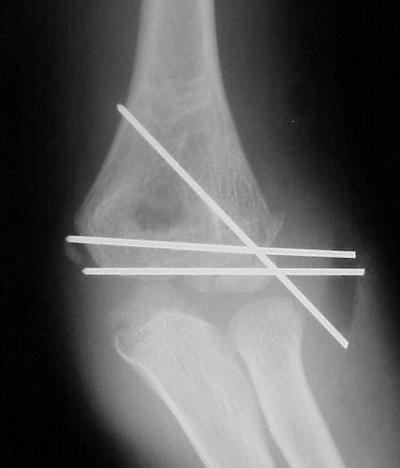

Open reduction and fixation:

Click for larger image